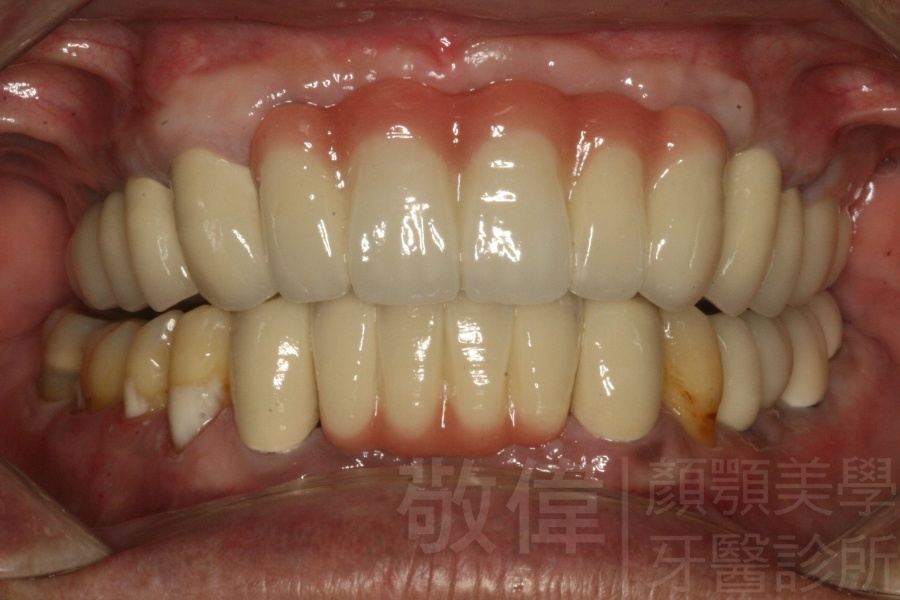

植牙的支台柱   裝上假牙完成